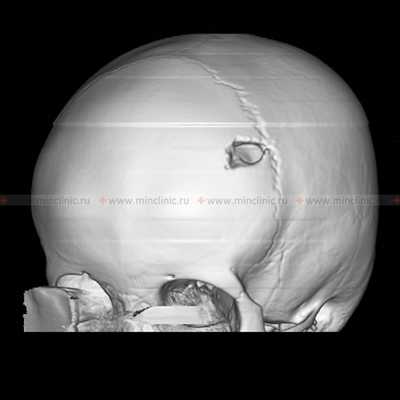

На компьютерной томографии (КТ) видно поражение черепа с классическими для эозинофильной гранулёмы скошенными краями.

Эозинофильная гранулёма протекает как очаговый остеолитический (растворение кости) процесс в кости с предпочтительной локализацией в своде черепа (чаще лобной кости), рёбрах, длинных трубчатых костях, тазу. Височная кость одна или с другими очагами — излюбленная локализация эозинофильной гранулёмы.

При инфильтративном поражении капсулы, эндооста лабиринта — у пациента наблюдаются симптомы поражения внутреннего уха. При рентгенологическом исследовании выявляется костный дефект без реактивного склероза в сосцевидном отростке или чаще височной кости. Иногда дефект костной ткани пальпируется через отёчные ткани. При распространённом процессе эозинофильной гранулёмы возможна деструкция (разрушение) всей пирамиды височной кости с симптомами поражения черепных нервов.